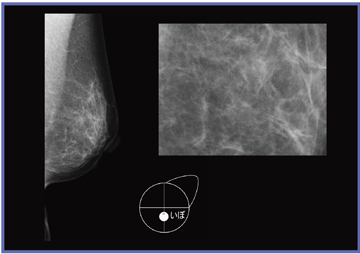

当初は,画像上に重ねてマーカーを入れていたが,読影する医師に先入観を与える可能性があるという指摘があった。そこで,医師に新しいマーカーを考案してもらい,メーカーに作成してもらった(図1)。具体的には,乳房の領域を示すモデル(a)と,画像上でそのまま大きさを比較できるように大きさを5mm(b),10mm(c)とした,ほくろやいぼを示すマーカー,手術瘢痕の形状を示すための5mmの十字マーカー(d)である。当センターではこれらのマーカーを使用することにした(サイズは実寸表示した場合の大きさ)。

図2は,ほくろの入力例である。右A領域にほくろがあったことがマーカーで示されており,画像上に認められる結節がほくろと一致するかを,読影医が判断することができる。図3は,いぼの入力例である。これまでは,コメントを記載するだけで,詳細な大きさや位置を伝えられずにいたが,マーカーの使用により,視覚的な判断が容易となる。また,図4は手術瘢痕の入力例である。以前は構築の乱れに合わせて画像上にマーカーを重ねていたが,新しいマーカーを使用することで,読影医は先入観を持たずに観察でき,技師の示した所見は参考情報として考慮することができるようになった。十字マーカーは1つずつ入力可能なため,直線や円弧状,乳輪に沿った形など自由に記載でき,ニュアンスを伝えやすい。